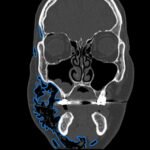

Subcutaneous emphysema (SE) is a rare but significant complication following dental procedures characterized by the presence of air in the subcutaneous tissue. This case report presents a 67-year-old male who developed right-sided facial swelling after tooth extraction, a procedure executed with high-power dental tools. Clinical findings included facial swelling and crepitus with no lip involvement, differentiating SE from an allergic reaction and hematoma. Diagnostic imaging through computed tomography (CT) and chest X-ray confirmed SE, showing diffuse subcutaneous air in facial and neck soft tissues. Initial management in the emergency department (ED) involved administration of antihistamines, corticosteroids, antibiotics, and otolaryngology (ENT) consultation with close monitoring for airway compromise. This case underscores the importance of including SE in differential diagnoses for post-dental procedure swelling, the effectiveness of CT imaging in SE identification, and the importance of early detection and treatment to prevent severe complications like respiratory and cardiac issues.